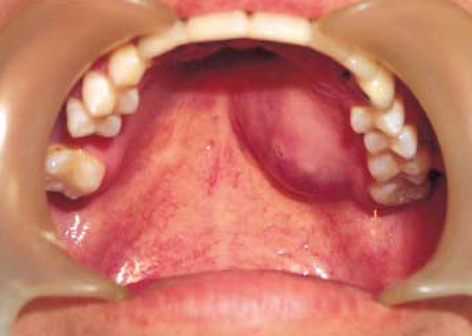

How to Identify and Treat Swelling of the Roof of the Mouth

Have you ever experienced an unexpected discomfort with the swelling of the roof of the mouth? That sudden swelling can catch you off...

Why Does the Roof of My Mouth Hurt After Eating?

Why Does the Roof of My Mouth Hurt Have you ever taken a bite of your favorite pizza or sipped a hot beverage,...